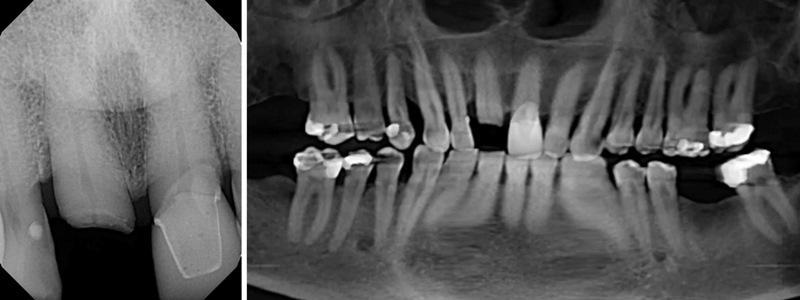

Для оценки сохранности корня на уровне десны и состояния окружающих тканей выполнена прицельная рентгенограмма зуба 1.1 (Фото 2, слева); для оценки зубных рядов выполнена панорамная реконструкция конусно-лучевой компьютерной томографии (КЛКТ) (Фото 2, справа). Проведено пародонтологическое обследование; остальная зубочелюстная система без патологических изменений. По зубу 1.1 отмечалась небольшая утрата кости с дистальной стороны, рентгенологических признаков периапикальной патологии не выявлено. Апикальнее корня зуба № 8, а также медиально и дистально от него имелась достаточная костная ткань для установки имплантата.

Фото 2. Прицельная рентгенограмма (слева) и панорамная проекция КЛКТ (справа), демонстрирующие перелом центрального резца и его взаиморасположение с окружающими структурами.